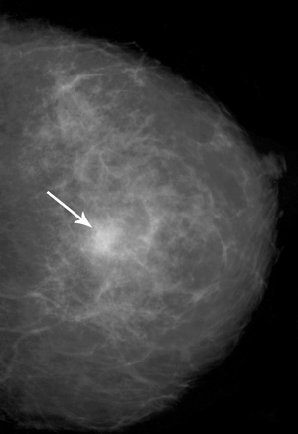

Radiologists from the University of Texas M. D. Anderson Cancer Center in Houston reported on a 57-year-old woman who presented with an ill-defined mass in the left breast on screening mammogram. The latter exam showed a 1.5-cm, high-density mass with indistinct margins.

A subsequent ultrasound exam revealed an ill-defined, hypoechoic mass. A histopathological exam of a biopsy sample "revealed a polymorphous infiltrate of histiocytes … with round nuclei (that) expressed S-100 protein, characteristic of Rosai-Dorfman disease," wrote Dr. Cynthia Pham and colleagues (American Journal of Roentgenology, October 2005, Vol. 185:2, pp. 971-972).

| Fifty-three-year-old woman with Rosai-Dorfman disease of the breast. Above, left breast craniocaudal mammogram shows 1.5-cm high-density mass with indistinct margins (arrow). Below, left breast longitudinal sonogram shows ill-defined, hyopechoic mass. Pham CB, Abruzzo LV, Cook E, Whitman GJ, Stephens TW, "Rosai-Dorfman Disease of the Breast" (AJR 2005;185:971-972). |